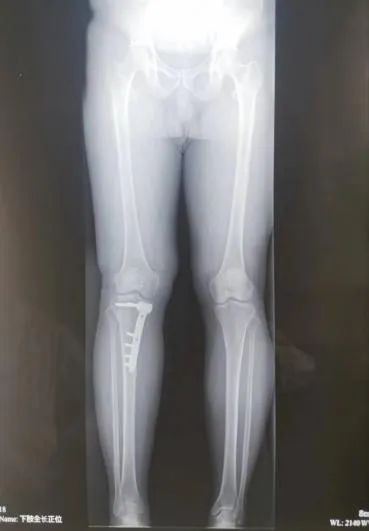

45岁的患者牛某,因5年前外伤致右胫骨平台骨折,未行手术治疗,伤后半年开始负重行走,致使右膝关节不稳定,且逐年加重。患者因右膝关节不稳定,不敢快速行走及下台阶,且摔倒数次,产生了恐惧心理。辗转多家医院后,均疗效不明显。 听闻“京长合作”首都医科大学附属北京积水潭医院每月定期派专家来长治二院骨科坐诊、查房、手术的医讯,主动要求北京积水潭专家手术治疗,近日来我院就诊要求住院手术治疗。 门诊经查体及阅读各项检查后以“右胫骨平台骨折畸形愈合”便收住院。 入院诊断: 1.右胫骨平台骨折畸形愈合 2.高血压病 住院期间,北京积水潭医院骨科吴宏华副主任医师结合查体及辅助检查,考虑患者畸形为关节外畸形,下肢力线向前内侧偏移,建议行胫骨内侧高位双平面截骨纠正对位及力线。考虑开放行双平面截骨,创伤较大,建议3D打印HTO截骨导板,在导报引导下行微创双平面截骨。在全身麻醉下在截骨导板引导下行截骨矫形术。 术后3天患者牛某持助行器下地行走,右膝关节不稳定感觉消失,恐惧心理消失,心情舒畅,对手术效果非常满意。 此次手术是在北京积水潭吴宏华副主任医师指导下,长治二院首次将HTO截骨技术应用于创伤骨科,是“京长合作”带给长治二院骨科发展的新动力,更为我市骨病患者带来的福音。 科室推荐 创伤骨科二病区隶属于长治二院骨科创伤专业,成立于 1978年建院之初,至今已历时 40 余年。创伤二病区现有开放床位 35 张,共有医师 10名(含返聘医师),护士 9 名。其中主任医师 1名,副主任医师 1 名、主治医师 6名、住院医师 2 名。 病区主任:李黎明,主任医师、长治市工伤医疗鉴定专家、北医三院进修学员,擅长复杂骨折的手术修复,尤其在骨盆骨折、关节周围骨折的手术治疗方面技术精湛。 创伤二病区诊疗疾病范围:肩胛骨骨折、肩(胸)锁关节脱位、锁骨骨折、肱骨近段骨折、肱骨干骨折、肱骨髁骨折、尺骨鹰嘴(冠突)骨折、尺桡骨骨折、桡骨远端骨折、各类型骨盆骨折、髋臼骨折、股骨头骨折、股骨颈骨折、股骨粗隆间骨折、股骨干骨折、股骨髁骨折、髌骨骨折、胫骨平台骨折、胫腓骨骨折、各类型踝关节骨折(韧带损伤)、各类型开放(闭合)性软组织损伤、陈旧性骨折不愈合、骨感染(骨髓炎)、内固定周围骨折、骨折非手术治疗、骨折康复指导等。 咨询热线 0355—3126025 主任医师 创伤骨科二病区主任 擅长复杂四肢骨折、骨盆骨折,脊柱骨折、颈椎病、腰椎管狭窄等的诊治。在肢体复杂损伤、脊柱退变疾病方面有较多深入研究。多次在北京、太原等省内外三甲医院进修学习,具有丰富的理论知识。 【学术任职】 长治医学院副教授、长治市骨科专业委员会委员、长治市足踝外科委员会委员、长治市医疗专家库成员,长治市工伤、司法鉴定专家组成员。在国家级省级专业杂志发表论文学术论文10余篇,在专业学术领域积累了丰富的临床经验。 医生推荐 徐彦芳 副主任医师 骨科学硕士 北京大学国内访问学者 【专业特长】 【学术任职】 咨询热线 李黎明主任 13097569000 徐彦芳医生 15635598825 供 稿丨徐彦芳 编 辑丨卞 晨 审 核丨雷 赫